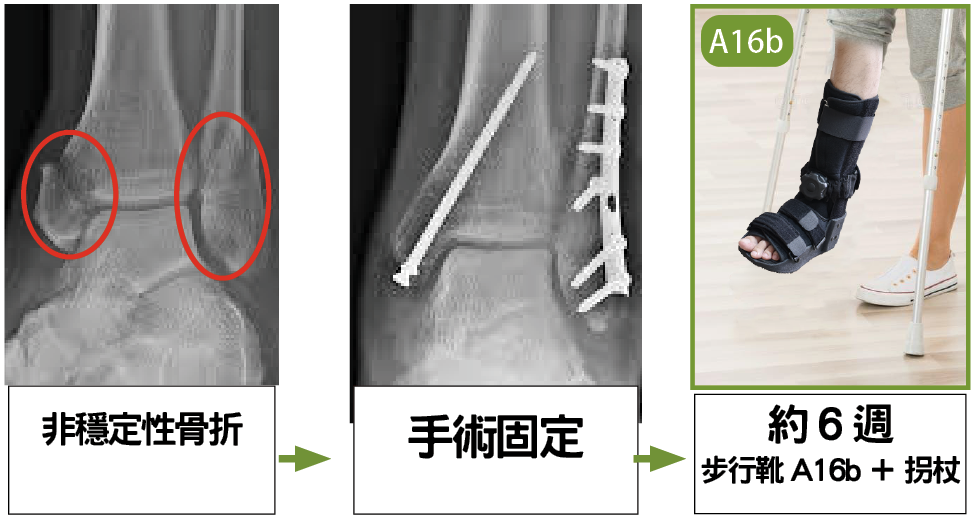

ii. 護具處理非穩定性移位骨折: 手術及術後復康

當患者出現不穩定或移位踝關節骨折時,需要進行手術復位,並使用螺絲和鋼板進行固定。

術後還需進行X 光檢查,以確保復位效果良好。術後6 週,應使用短身步行靴(A16b),同時使用拐杖,從而保護手術傷口和固定足踝,並減輕負重或擺動引起的疼痛,此期間可用拐杖作漸進式負重復康比較安全。